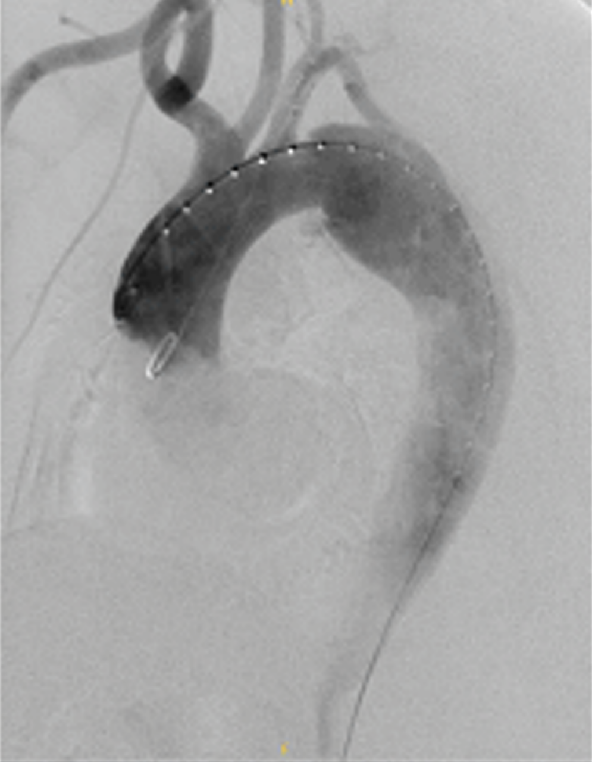

通过下面4个具体病例进一步说明TEVAR在治疗复杂型B型主动脉夹层中的治疗原则、注意事项及应用。

★病例1

28岁男性,急性复杂型B型AD,急诊TEVAR治疗

★病例4

急性复杂性AD